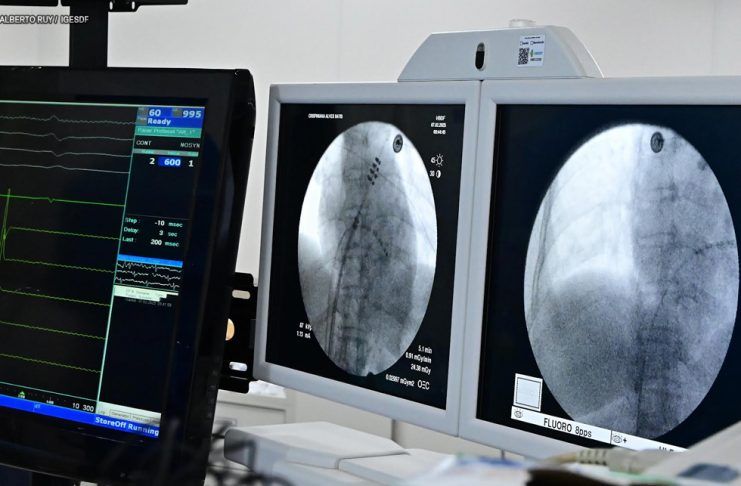

HBDF realiza tratamento de arritmias cardíacas com a ablação e aplicação de pulso de elétrons – Foto: Alberto Ruy/ IgesDF

A eletrofisiologista invasiva Carla Septimio Margalho, supervisora do Programa de Residência em Eletrofisiologia Clínica e Invasiva do Hospital de Base, explica que a técnica é revolucionária. “A PFA utiliza uma tecnologia nova, desenvolvida recentemente, que permite a realização da ablação com mais segurança e eficiência. O procedimento, chamado ablação de fibrilação atrial com aplicação de pulso de elétrons, é um marco no tratamento da arritmia e já tem mostrado resultados promissores”, destaca.

“O que antes levava 8 a 10 horas e exigia UTI, agora pode ser realizado em cerca de 55 minutos. O paciente pode ser encaminhado à enfermaria e recebe alta em poucos dias, o que reduz riscos, otimiza o atendimento e diminui custos”, explica o cardiologista Henrique Cesar.